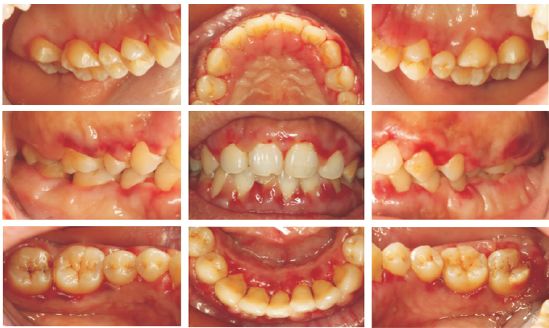

检查:全口牙龈红肿,可见出血点,龈上牙石(+)(图1)。

图1  病例1患者口内相